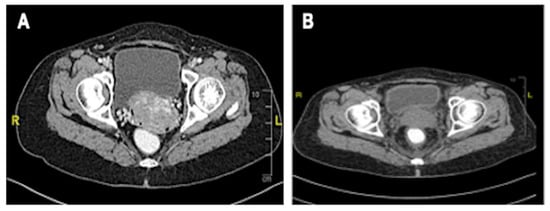

An examination under anaesthesia noted normal vulva and smooth vagina with no nodularity. However, a small raw area (1 × 1 cm) was noted at the upper 1/3 of the vagina (Figure 2A). An exophytic growth of 4 × 4 cm, occupied 9 to 5 o’clock position of the friable cervix which bled on touch (Figure 2B). Cystoscopy noted normal bladder mucosa and no evidence of tumour invasion. The assessment showed clinical staging of the cervical cancer as stage 2A. Histopathological examination of the upper 1/3 posterior vagina and cervix was consistent with human papillomavirus (HPV)-associated keratinizing squamous cell carcinoma (Figure 3). The tumour cells showed block positivity towards P16 immunohistochemical stains (not shown).

Figure 2. Vaginal and cervical examination. (A) Remnant cervical growth and small raw area (1 × 1 cm) at posterior upper 1/3 of vagina; (B) Exophytic cervical cancer (4 × 4 cm) occupying 9 to 5 o’clock position of the cervix, was friable, and bled on touch.